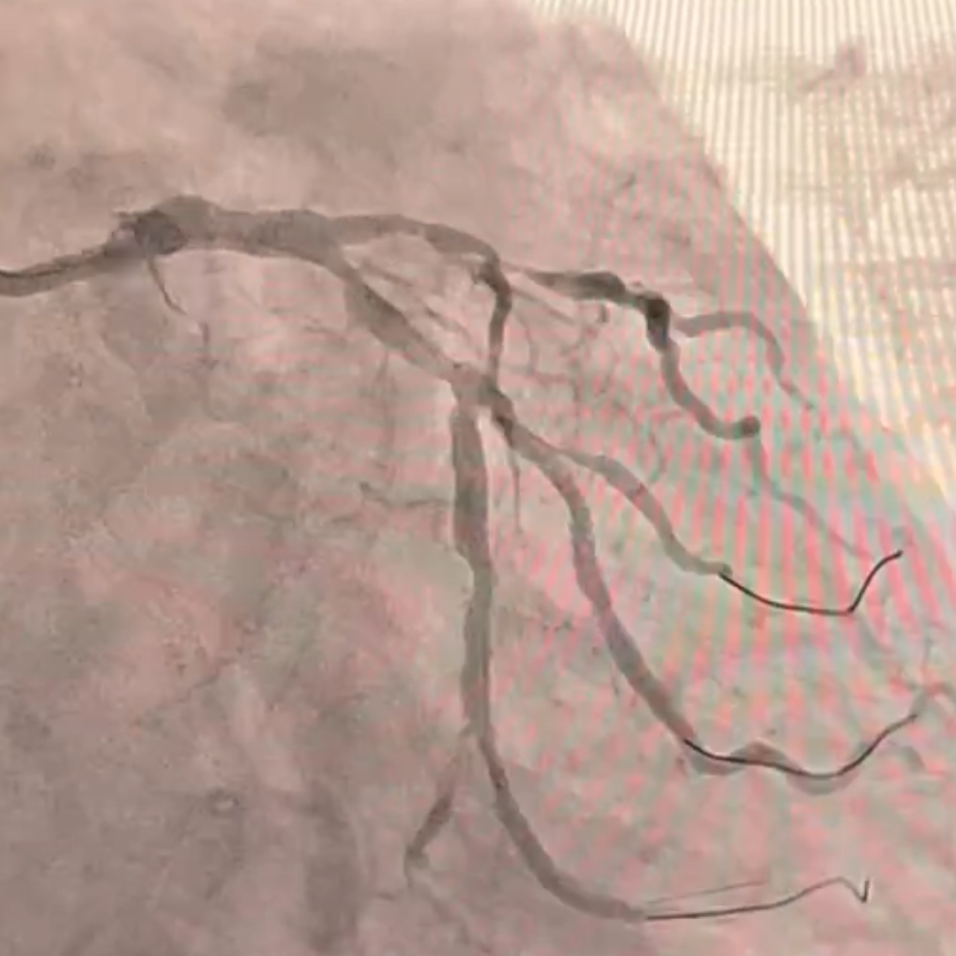

冠脉造影:前降支弥漫性病变,近段与间隔支形成分叉病变,最窄可见约90%狭窄。回旋支近段70%狭窄,远段弥漫性病变,最重处95%狭窄,远端可见侧枝向PDA供血。

冠脉造影:前降支近段80%、中段90%狭窄,第一对角支近段70%狭窄,回旋支近段70%狭窄,第一钝缘支90%狭窄。

支架植入:串联植入2枚3.5×28mm/3.0×33mm支架覆盖LAD近中段钙化病变,通过IVUS实时优化后扩策略(序贯20/22atm高压扩张),最终支架膨胀、贴壁满意。